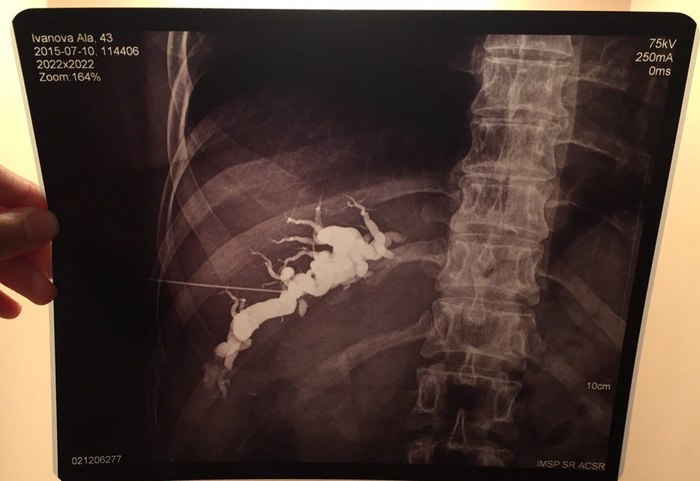

Около месяца назад Алле поставили страшный диагноз - холангиокарцинома - злокачественная опухоль, исходящая из мутировавших эпителиальных клеток желчных протоков. Болезнь очень редкая, лечению как я понял поддаётся тоже крайне редко и очень тяжело. Опухоль мешает оттоку желчи из печени, из-за чего, насколько я понимаю(возможно не совсем верно), нельзя ни назначить нормальную химию, ни сделать операцию. Замкнутый круг.

Диагноз и снимки: